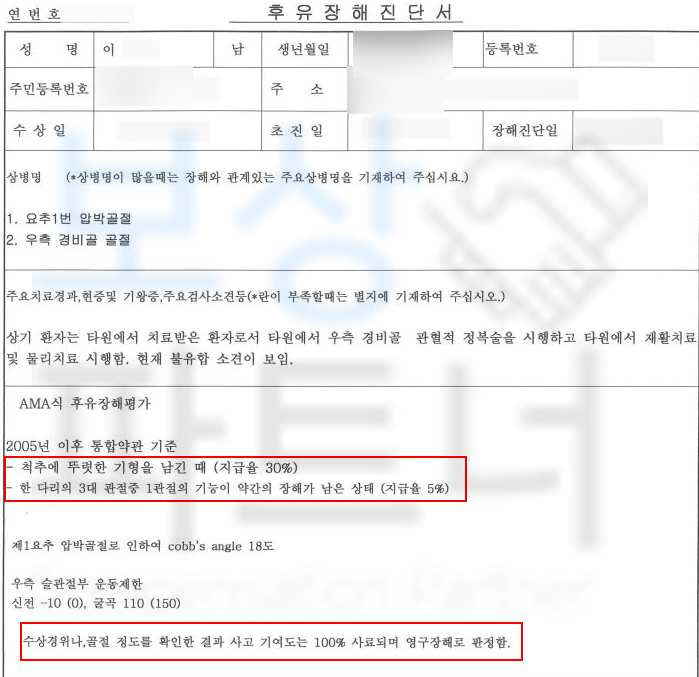

오늘은 척추압박골절을 예로 들자면

문제는 “장해”의 잔존을 증명하기 위해서는 사고 경위, 의료 전문의의 후유장해진단서 기존 질병의 기여도 등등의 분석이 필요합니다.